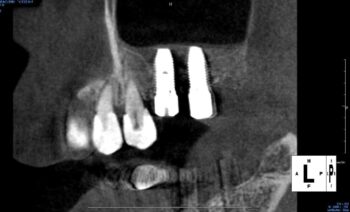

インプラントの傾斜埋入

従来のインプラントはアゴの骨に対して垂直に埋め込まれることが当たり前でしたが、傾斜埋入は、斜めに埋め込んだインプラントで義歯を支えることを可能とする治療法です。

埋め込む位置や角度の計算が複雑になるため、高い診断力と技術力が求められる治療法といえます。

事前に歯科用CTで骨の状態を把握し、徹底的なシミュレーション、埋入する技術がないと行えない高度なインプラント技術です。